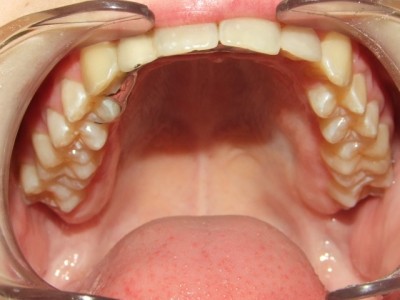

Na behandeling